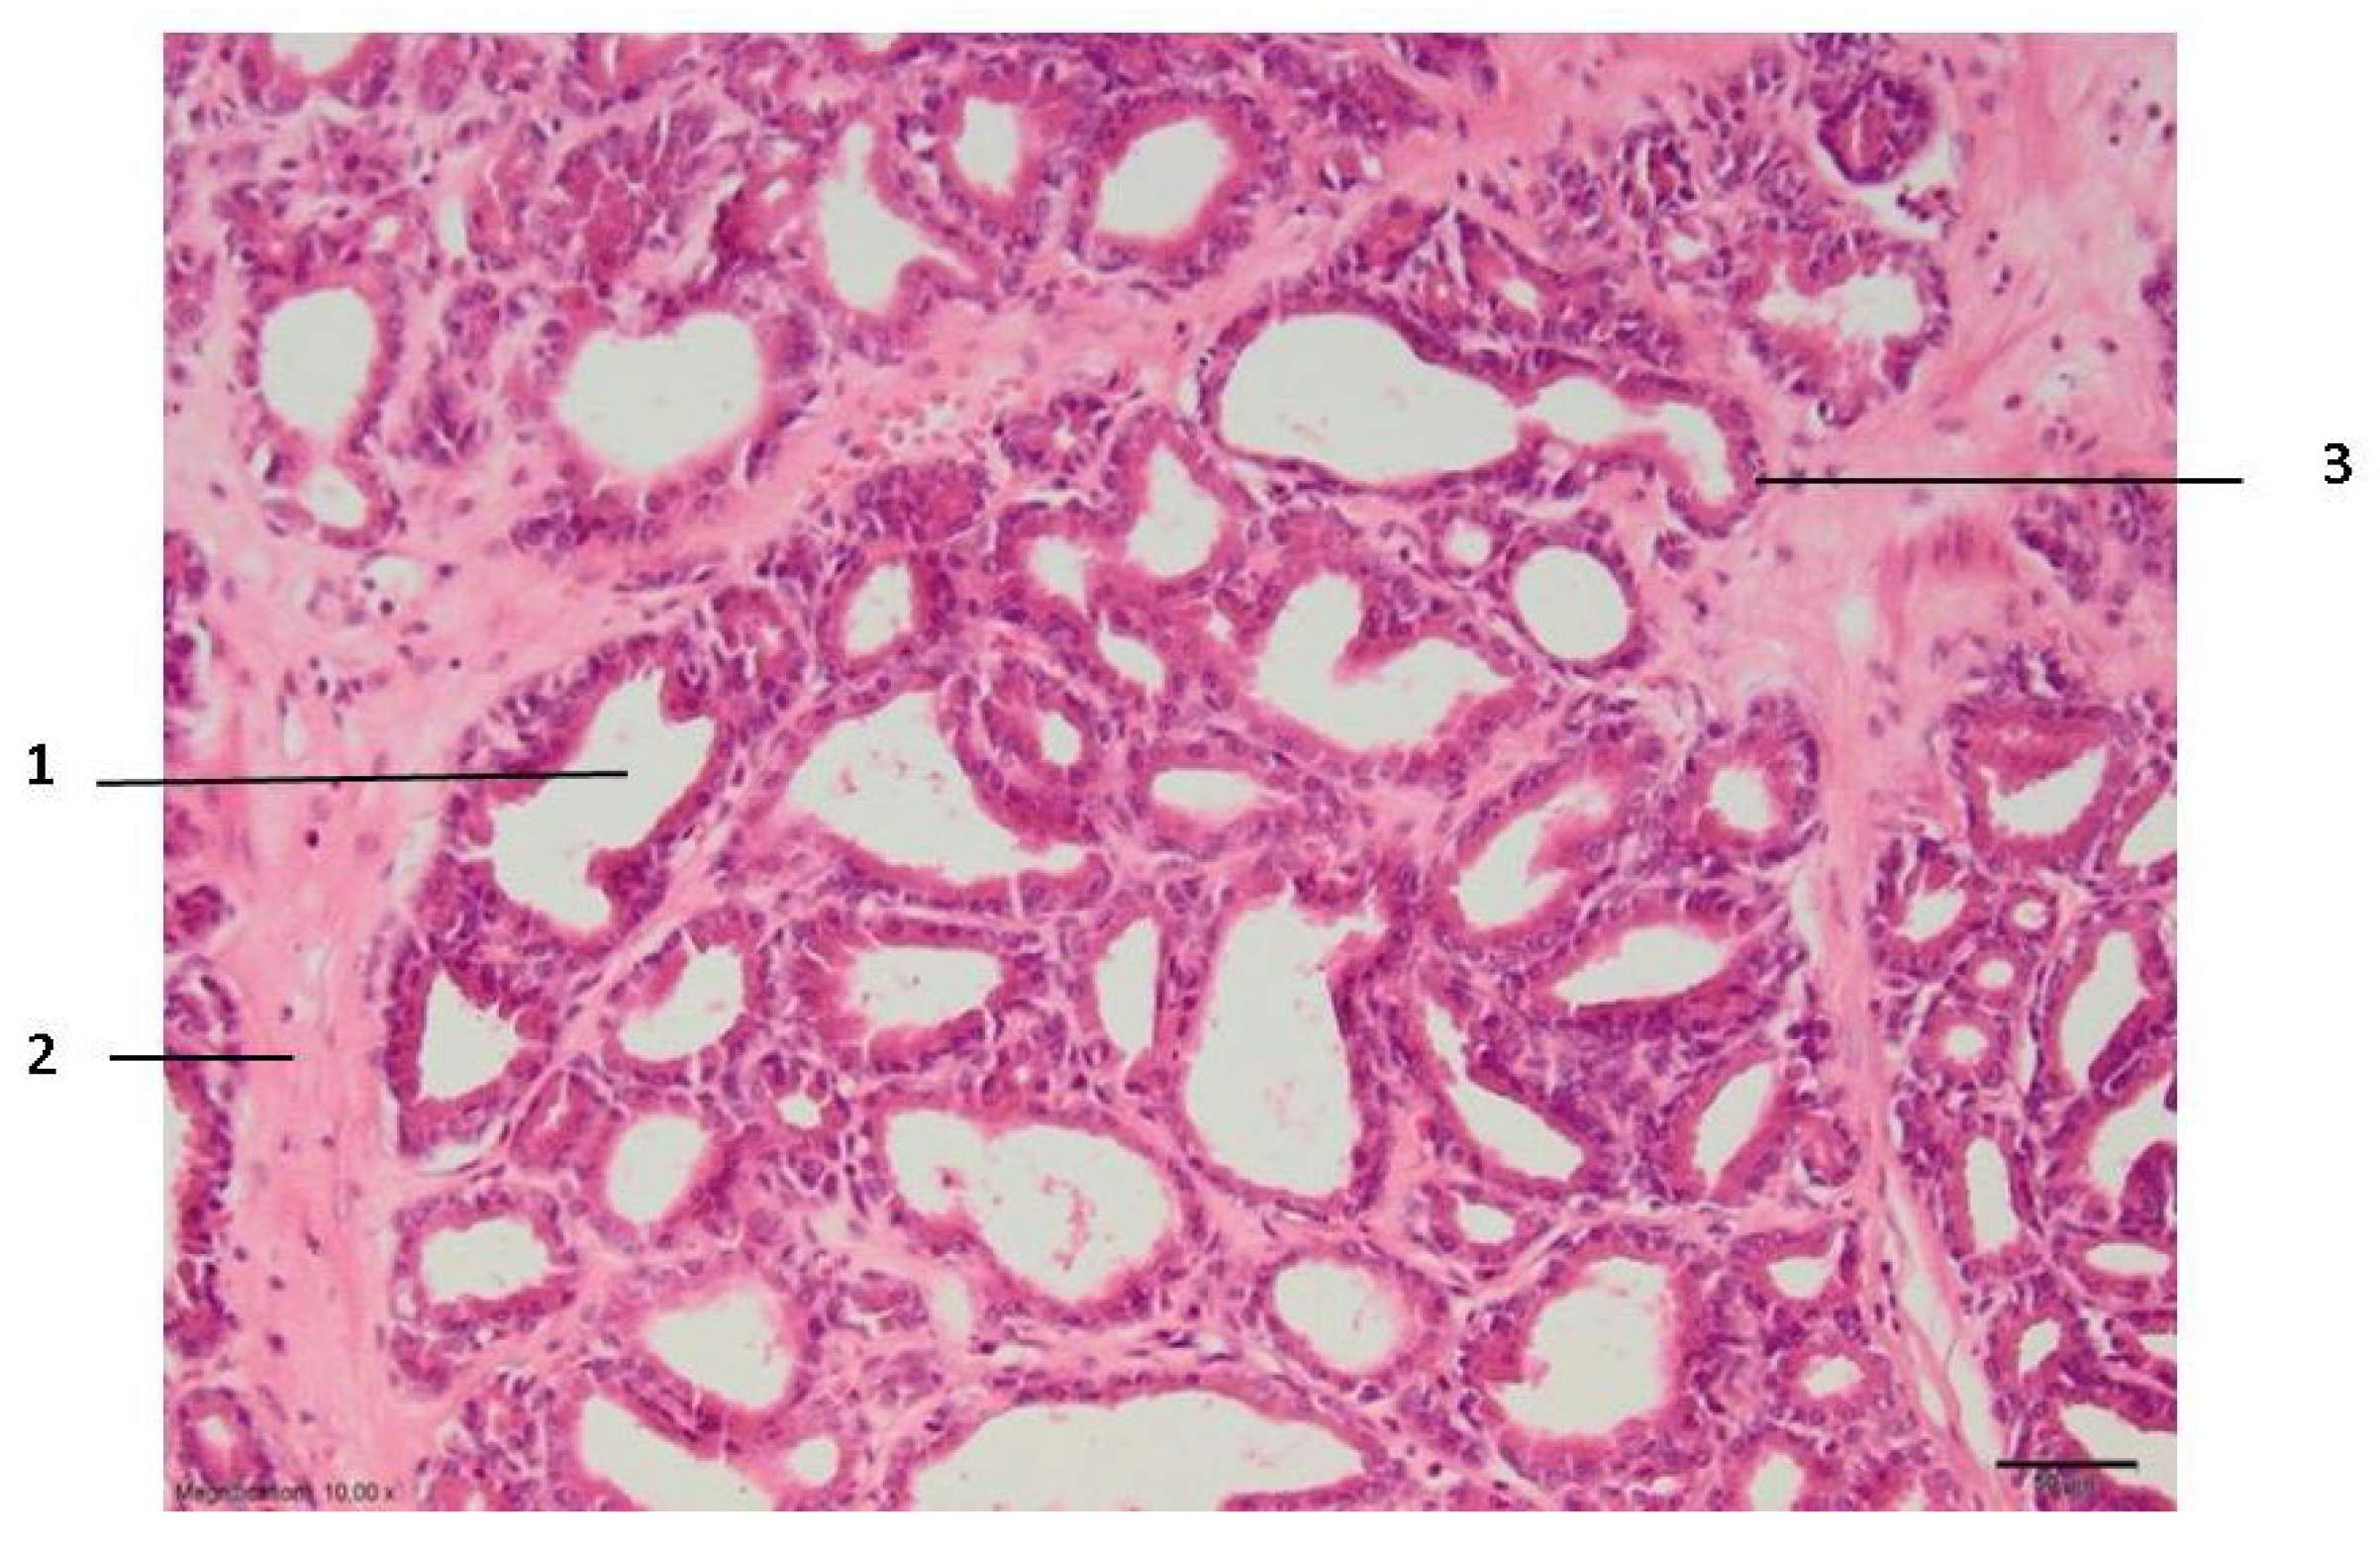

Figure 3.

Zone III of the prostate lesion: 1—stroma; 2—glandular epithelium; 3—prostate alveolus. Microtome-cut sections of prostate samples were stained with hematoxylin and eosin.

In zone III, which can be relatively called the necrosis zone, the tissues are affected by coagulative necrosis but retain their shape; however, in our case, it is not fully formed because the gland boundaries are preserved, although with desquamated epithelium cells. The cytoplasm of cells is filled with large granules visualized with the dye eosin. In addition, the nuclei of such cells are dense and compact or even invisible, and necrotic epithelial cells without nuclei predominate. Edema and slight extravasation of red blood cells are observed in the stroma, as well as degeneration and necrosis of non-striated muscle cells (Figure 3). Such an effect could be explained by the fact that the glandular epithelium is more sensitive than the stroma, which consists of muscular and connective tissue cells. The normal glow of collagen fibers is visible under polarizing light.